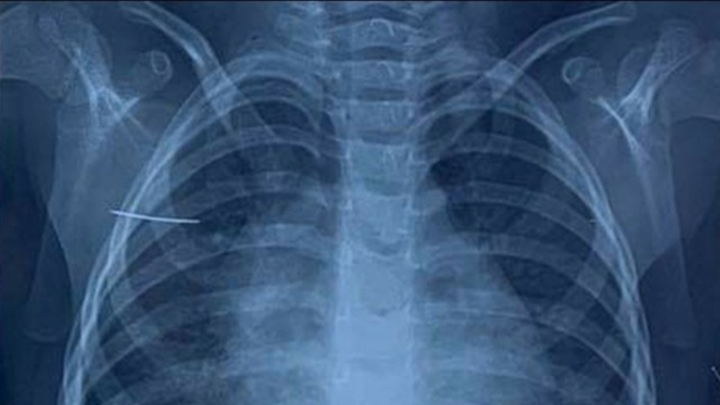

Kim khâu 4cm trong cơ thể bé gái 3 tuổi

Theo gia đình bệnh nhi, trong lúc chơi đùa bé gái ở huyện Bình Giang, tỉnh Hải Dương đã vô tình nằm đè vào chiếc kim khâu.

Các bác sỹ cho biết đây là trường hợp bệnh nhi vào viện trong tình trạng rất nặng, có thể ảnh hưởng đến tính mạng nếu không được chẩn đoán, xử lý kịp thời.